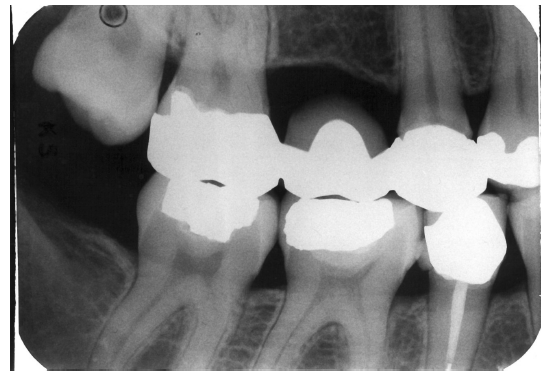

Recurrent Caries

Recurrent caries is the condition in which carious lesions develop or extend along the margins of existing restorations. A diligent search for recurrent caries should be made whenever radiographic images detect:

• interproximal restoration overhangs

• open margins on restorations

• restorations which appear to end short of preparation margins; or

• restorations which appear unusually shallow as judged by the thickness of the restorative material.

Radiographically, recurrent caries presents as radiolucent lines that extend inward from the tooth surface along a restoration or as radiolucent zones, which appear to lie completely beneath the restoration without any observable communication with the tooth surface. As mentioned previously, the junction of a restored tooth and the restorative material should appear sharp and distinct, and, as a rule, recurrent caries should be suspected whenever radiolucencies are present between the tooth and the restoration.

In Figure 4, recurrent caries appears at the mesial of tooth #3 and #4, and the distal of tooth #28. Also, note areas of interproximal caries on teeth #5-6.

Figure 4 - Recurrent Caries

Figure 4